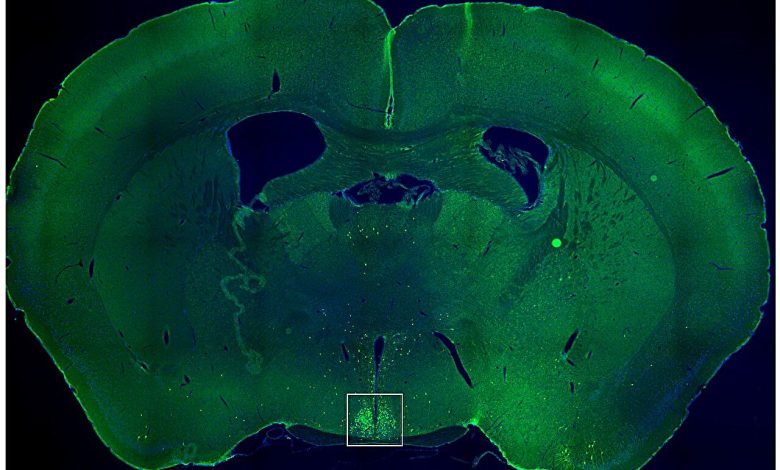

Esta imagem mostra uma fatia fina do meio do cérebro de um camundongo, com a região conhecida como núcleo supraquiasmático (SCN) cercada por uma caixa branca. Os pequenos pontos verdes marcam as células cerebrais que reagem ao hormônio da fome grelina. Quando as células sensíveis à grelina no SCN são desligadas durante o tempo normal de descanso do rato, os animais comem menos e perdem peso. Crédito: UT Southwestern Medical Center

Estas observações sugerem que circuitos específicos de neurónios que afectam a alimentação e o metabolismo podem funcionar de forma diferente em vários momentos do dia. Zigman, Singh e seus colegas levantaram a hipótese de que um desses circuitos poderia estar no núcleo supraquiasmático (SCN), uma parte do cérebro que estabelece ritmos circadianos por todo o corpo com base na luz recebida pelos olhos.

Pesquisas anteriores no Laboratório Zigman mostraram que alguns neurônios do SCN são estimulados pela grelina, um hormônio que estimula a alimentação e retarda o metabolismo para estimular o ganho de peso. No entanto, o significado dessas descobertas não era claro.